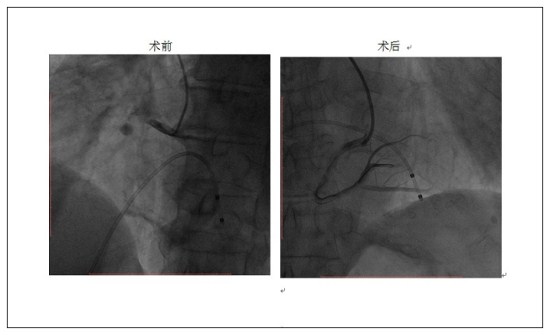

术中急诊冠脉造影发现患者的右冠近开口以下完全闭塞,前向血流TIMI0级。在成功开通右冠状动脉后,植入支架1枚。由于患者血栓负荷重,复查造影右冠状动脉出现严重无复流及慢血流,给予血栓抽吸及反复冠脉内应用药物后,右冠血流恢复,前向血流TIMI2-3级。